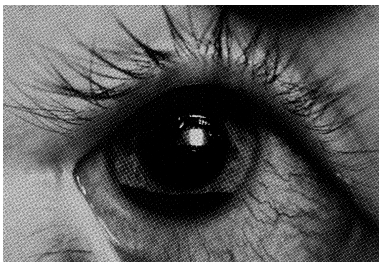

TRAUMATISME OCULARE: CONTUZIILE, PLAGILE OCULARE

TRAUMATISME OCULARE Se clasifica in contuzii ale globului ocular, plagi ale globului ocular si arsuri oculare (arsurile au fost tratate in capitolul corneea). Foarte important in fata unui traumatism ocular este staCiteste tot ... 1869 cuvinte

+ cu poze |